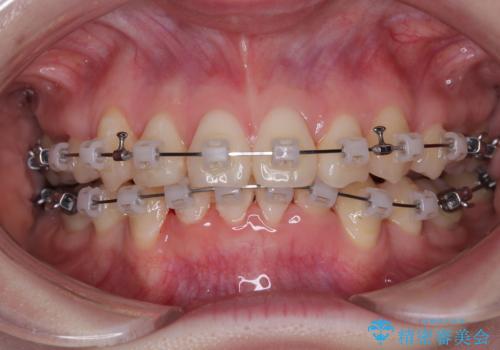

上下の八重歯とクロスバイト ワイヤー装置での抜歯矯正

上下ともに八重歯が顕著であり、前歯のクロスバイトがあったため、上下左右の第一小臼歯4本を抜歯し、ワイヤー装置での抜歯矯正を行うこととしました。

20歳ということもあり、歯の移動速度が非常に速く、1年強という短期間であっという間に治療を終えることができました。